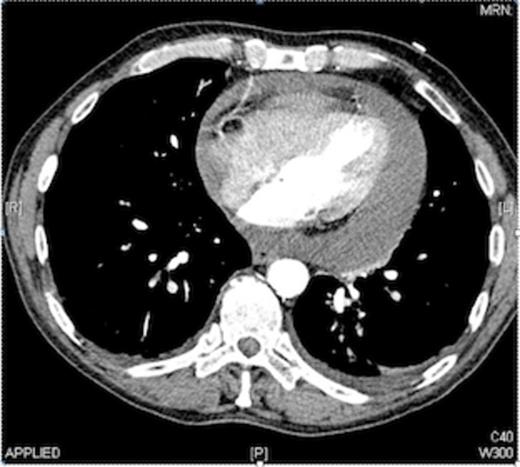

The CT findings were a moderate to severe pericardial effusion, with a fluid rim of approximately 2 cm, around the whole pericardium (as shown in Fig. 1).

The effusion was drained under ultrasound guidance. 900mls of blood stained fluid was aspirated. His blood pressure improved dramatically and stabilised, the patient felt immediately better, his breathing eased, and his shortness of breath settled.